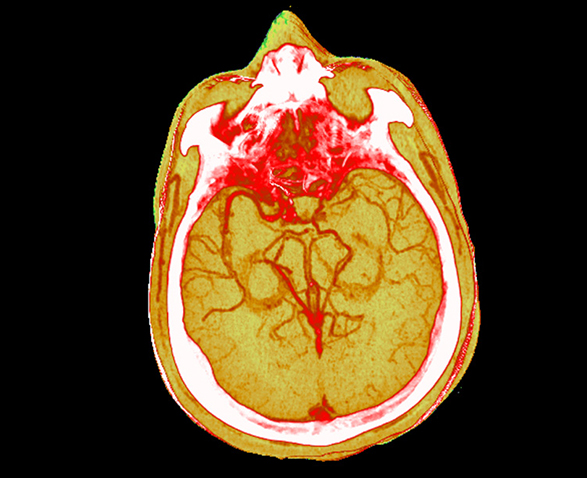

Galvos ir kaklo kaulų pašalinimas: neurologiniai tyrimai tampa nesunkūs ir gali būti atliekami KT konsolėje.

„ClearView“ – iteracinis apdorojimas projekcijos ir vaizdo erdvėse leidžia sumažinti dozę.